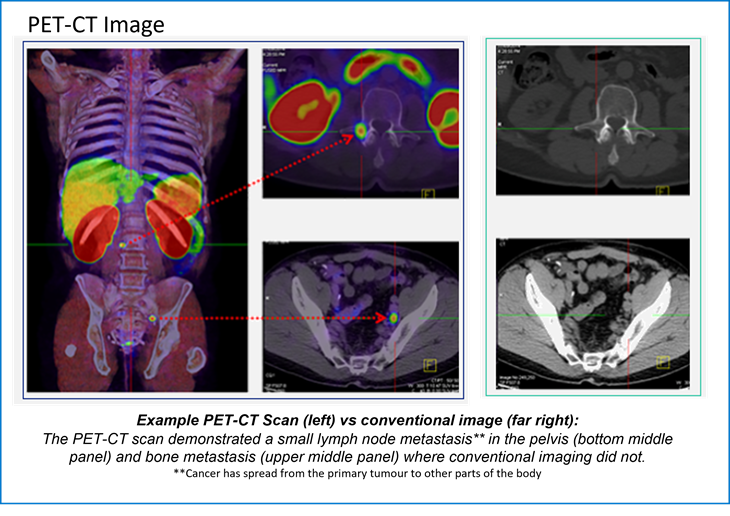

The PET-CT images